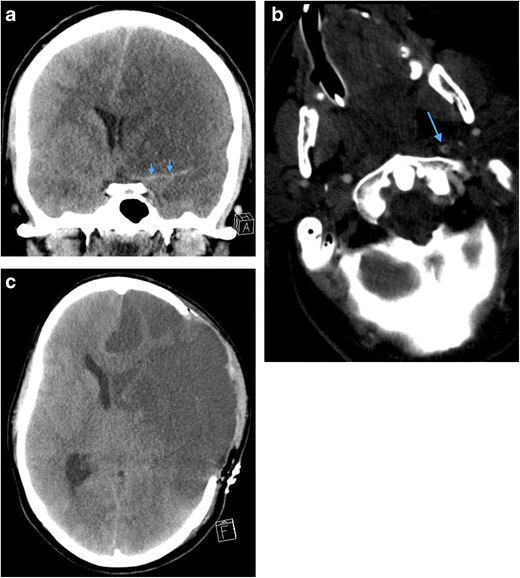

a Coronal reformatted non-contrast CT brain image of a 34-year-old man who sustained a penetrating knife injury to the left zone 2 of the neck requiring emergency surgical neck exploration prior to imaging assessment because of catastrophic haemorrhage. Therefore, pre-treatment CT and MDCTA were not performed because of the clinically evident active life-threatening haemorrhage on arrival in the emergency department. The non-contrast CT brain assessment was performed immediately prior to the post-operative MDCTA (b) and demonstrates acute thromboembolic “malignant” left anterior circulation infarction: there is already ischaemic demarcation of both the left middle and anterior cerebral artery territories with severe subfalcine herniation and midline shift; hyperdense thromboembolus is evident in the left middle cerebral artery (arrows) and proximal left anterior cerebral artery. b Axial image of MDCTA of the same patient as in a performed immediately post-operatively following internal carotid artery repair reveals a tail of extensive intraluminal thrombus extending distally from the site of vessel injury and repair (arrow). c Axial non-contrast CT brain of the same patient as in a and b performed 48 h later. The patient has undergone interval emergency left decompressive hemicraniectomy: the left anterior circulation low attenuation infarction is more established and the significant mass effect, subfalcine herniation and intracranial pressure related to swollen oedematous parenchyma have been ameliorated by hemicraniectomy. Unfortunately, brain-stem death was confirmed 12 h later